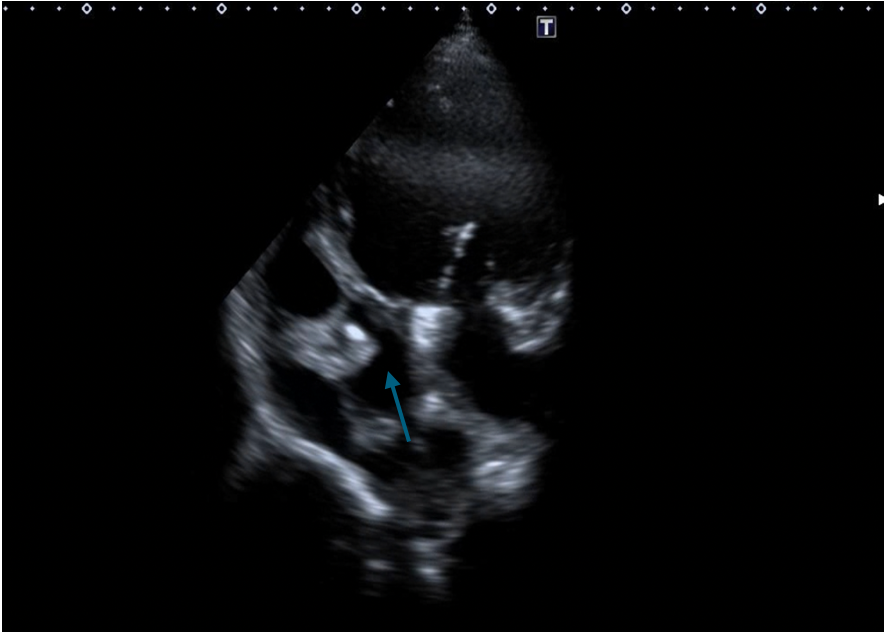

We chose an appropriately sized occluder, which was 20% greater than the entrance diameter of the ruptured SVA. The selected occluder with its attached delivery cable was inserted through the delivery sheath from the venous route, and its aortic disc was deployed in the ascending aorta. Positioning of the device (an ADO single-disc device of 6-8 mm) was then confirmed under transthoracic echocardiography (Figures 4A-C, Videos 4A-C).

Figure 4. (A) Positioning of the Amplatzer Duct Occluder (ADO) device (Abbott) (blue arrow). (B) Transthoracic echocardiography. (C) No residual shunt observed across the defect following device placement on transthoracic echocardiography.

(Figure 4A)

Gentle traction was exerted on the delivery cable to confirm seating of the left disc on the aortic side without slippage into the ruptured SVA. The rest of the occluder was deployed on the right side across the lesion (Figure 5A-B, Videos 5A-B).

Figure 5. (A) Device deployed (purple arrow). (B) Transthoracic echocardiography.